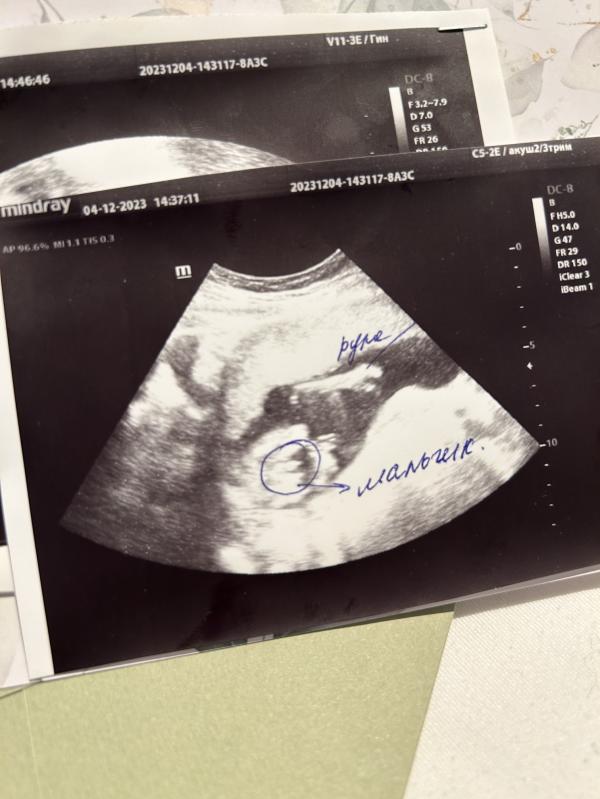

Девочки ,была на узи )

Вот вердикт ,но хоть убейте не вижу я тут мужское достоинство 😂 а вы ? Помогите разобраться🙏🏻точно ли мальчик 😅

Вот овалы по бокам - это ножки согнутые, а между ними - он, тот самый орган😄

Я думаю вы не можете понять, потому что не поняли в какой позе малыш. Это как бы вид снизу на фото узи.. Посередине достоинство, по бокам ножки)))

Очень видно ) мошонка и писюн, 100% мальчик

На узи мальчик, отлично видно мошонку и пенис

Да там вон яички и половой орган прям на первом фото в кружочке, там сложно не увидеть. Я так на Узи поняла кто у меня, сама сказала врачу, что мальчик.